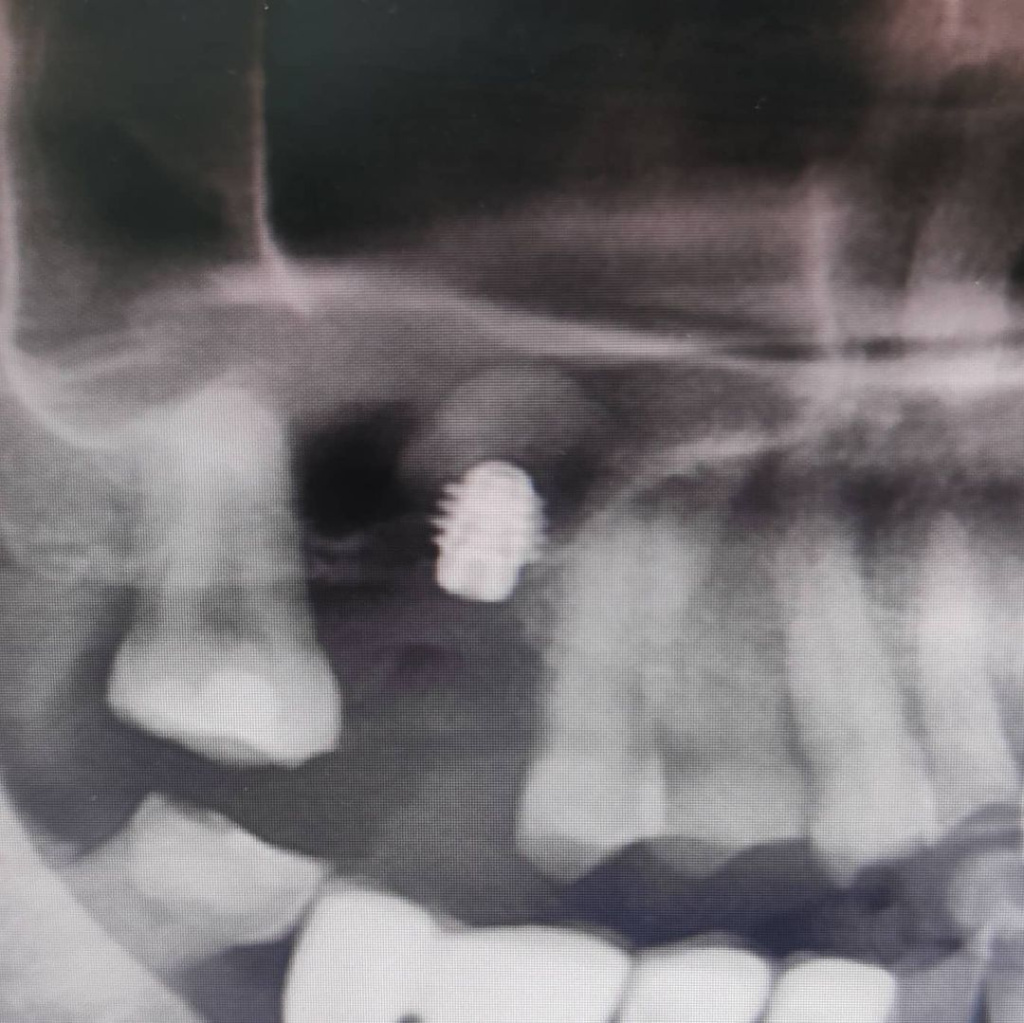

Короткие широкие имплантаты AnyRidge - это идеальный вариант для имплантации при недостатке высоты кости на верхней челюсти.

Через 2 месяца пациенту проведен гребневой синус-лифтинг с одномоментной установкой супер-короткого имплантата AnyRidge. Вся процедура заняла не более 15 минут. Протезирование запланировано через 12 недель после имплантации.